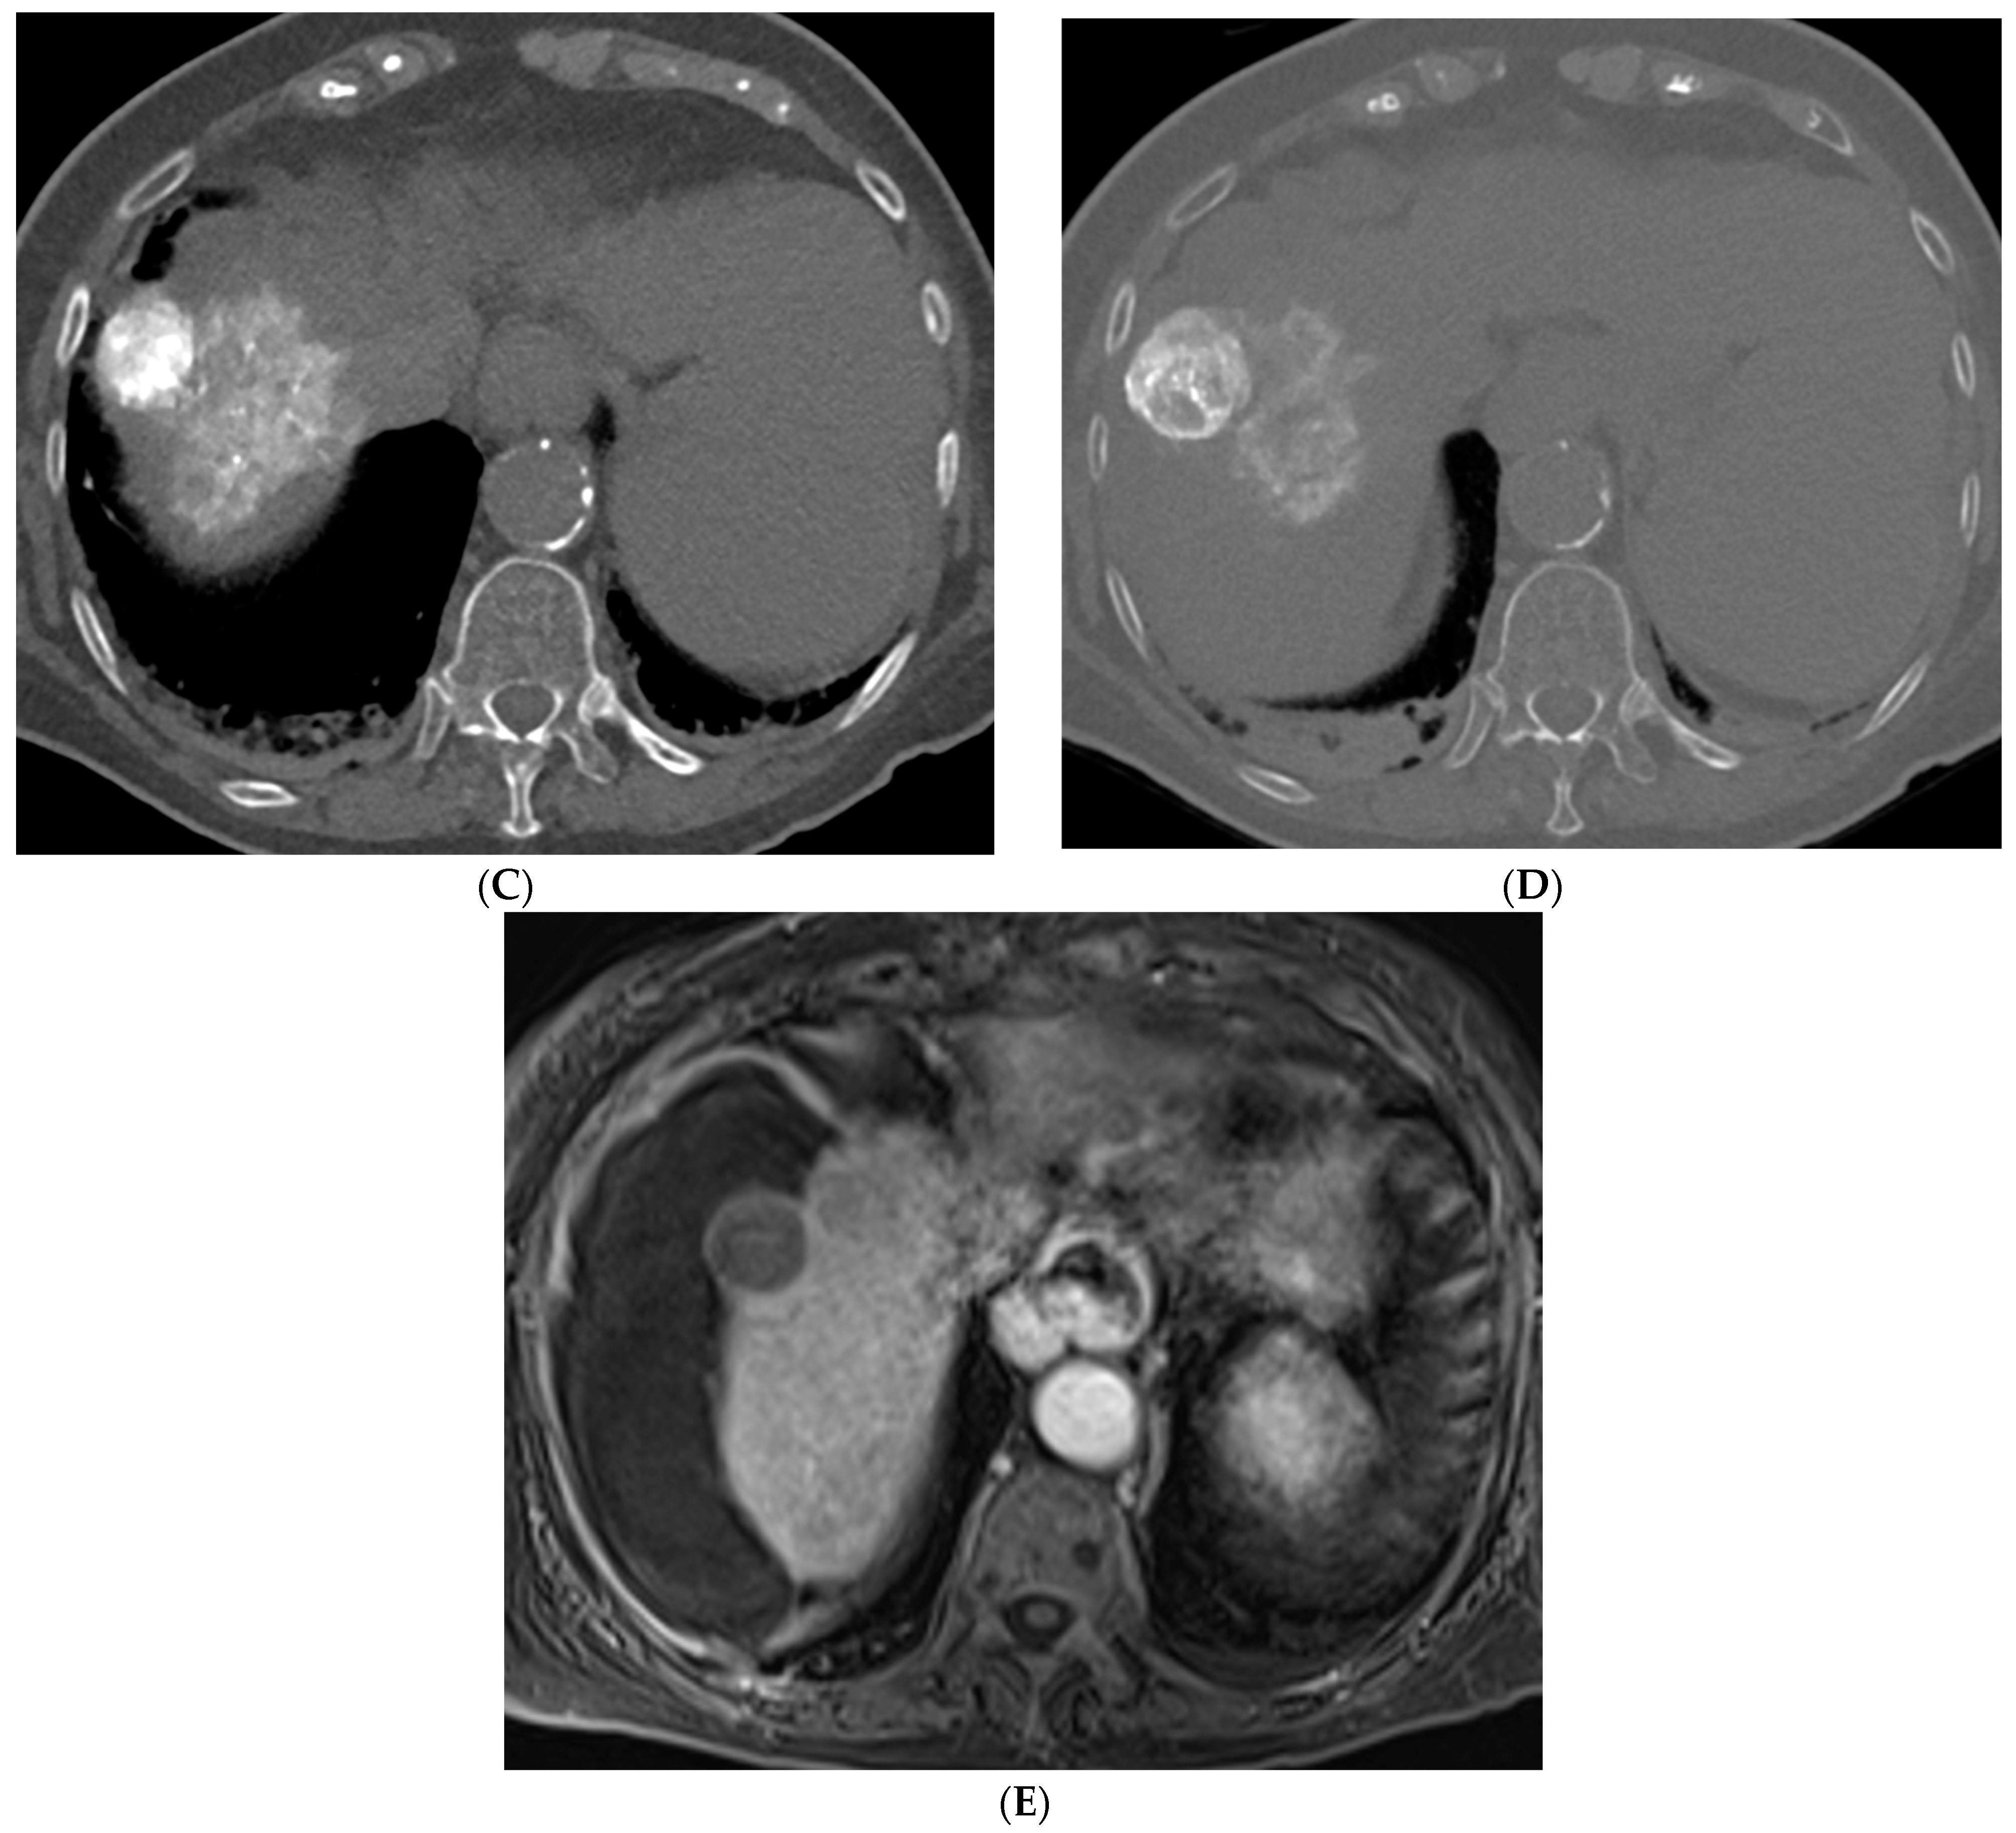

Figure 3.

73-year-old man with non-cirrhotic HCC treated with 90Y radiation segmentectomy. (A) Arterial phase MRI showing a 4 cm arterially enhancing lesion in hepatic segment 5. (B) Delayed phase MRI showing washout of the lesion. (C) Intraprocedural CTA demonstrating supply to the posterior aspect of the mass from one of the segment 5 branch arteries. (D) Intraprocedural CTA demonstrating supply to the anterior aspect of the mass from a separate segment 5 branch artery. The Y90 dose was delivered as a split dose between these two arteries. (E) Follow up arterial phase MRI 3 months after treatment demonstrates wedge-shaped post-treatment changes in hepatic segment 5 with expected parenchymal enhancement and capsular retraction with no residual enhancement of the targeted tumor. (F) Follow up delayed phase MRI demonstrates no wash-out of the enhancing parenchyma to suggest residual viable tumor, consistent with complete response.